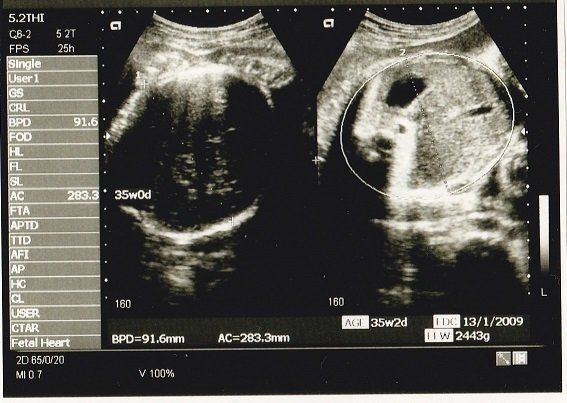

AC(おなかの周囲の長さ)などから、赤ちゃんの推定体重を計算するようです。赤ちゃんのおなかも大きくなっていますが、お母さんのおなかもぱんぱんです。

妊娠35週目のエコー写真 いよいよ出産へ

妊娠9カ月になり、いよいよ出産に向けての準備段階です。母親学級に参加して、出産についていろいろと勉強しました。待望のわが子に会えるまで、あと少しです!

私の息子は生まれたときから髪がふさふさでした。このころから髪が伸びていたのかな?